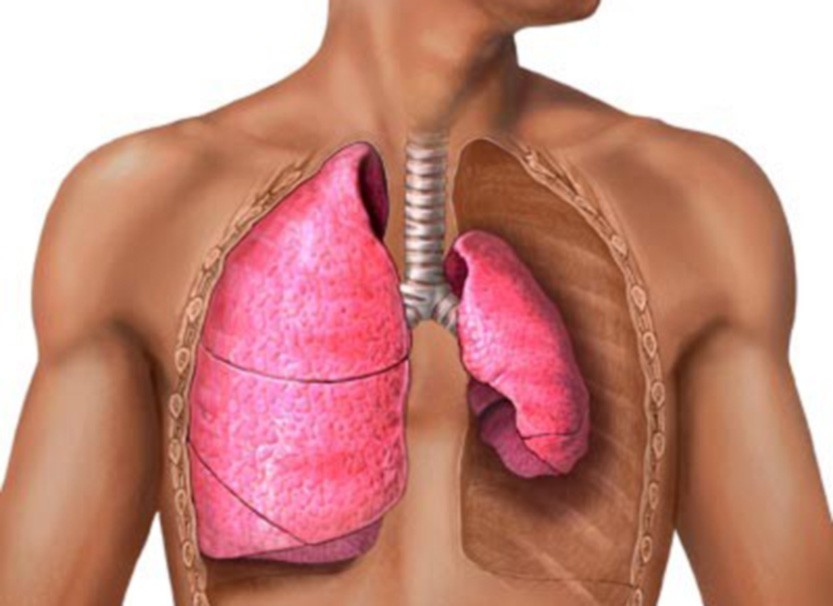

Схемы дыхания: Пневмоторакс на изображениях